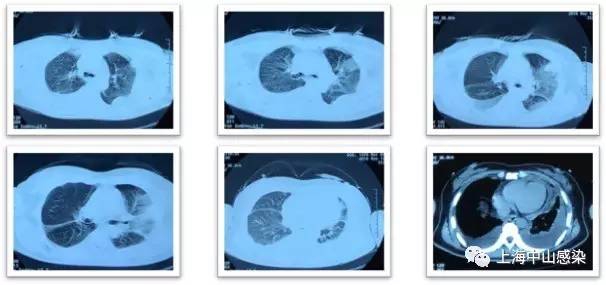

二进制 发表于 2017-1-6 05:01 “患者虽然做了血培养,但缺少痰培养。做痰培养。” 主题内容提及:患者为干咳、无痰。痰培养、涂片不能 ...